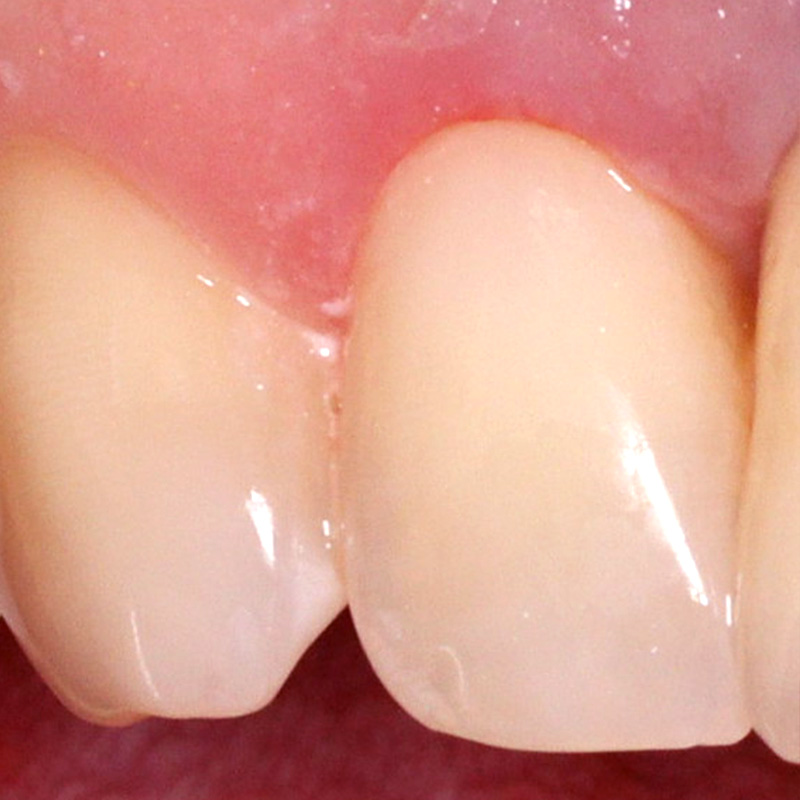

Пациент обратился с жалобой на эстетический недостаток в области нижнего зуба справа. После обработки кариозной полости врач выявил глубокий кариес. Дно и стенки полости плотные, гладкие, блестящие, при зондировании крепетируют. Реакция на холод слабоболезненна, на перкуссию — безболезненна. Диагноз — хронический глубокий кариес.

Ход лечения:

- введение анестезии Sol. Articaini vs. Adrenalini 1:200000 1.8 ml;

- наложение системы OptaGate;

- установка ретракционной нити UltraPack 00;

- механическая обработка кариозной полости;

- медикаментозная обработка полости раствором хлоргексидина 2%;

- пломбирование Vitremer (A3);

- микроконтурирование и макроконтурирование пломбы.